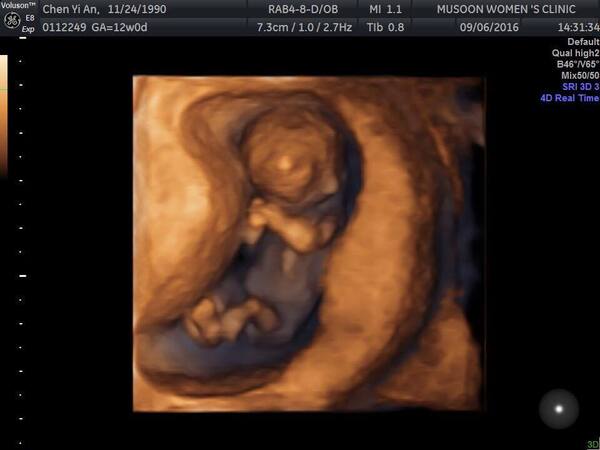

在2016年6月我們的第一個寶寶棉花糖來報到了,我們真的非常開心 ❤️

懷孕已經三個多月,我的爸爸很擔心工作時身旁的人沒有辦法注意孕婦的狀況,選在此刻公開,也讓我的家人安心。